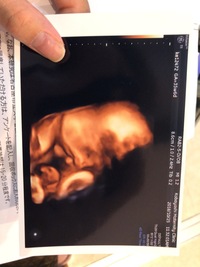

クリフムの4dエコー写真 妊婦健診 高齢出産に挑戦した夫婦のダウン症児子育て日記